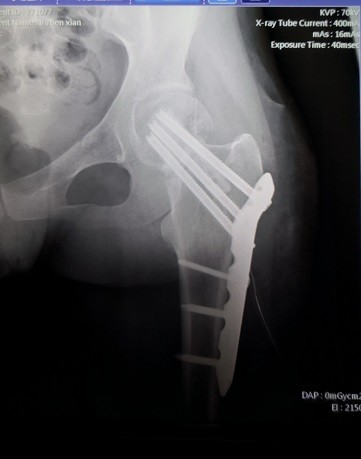

游离腓骨治疗股骨颈不愈合